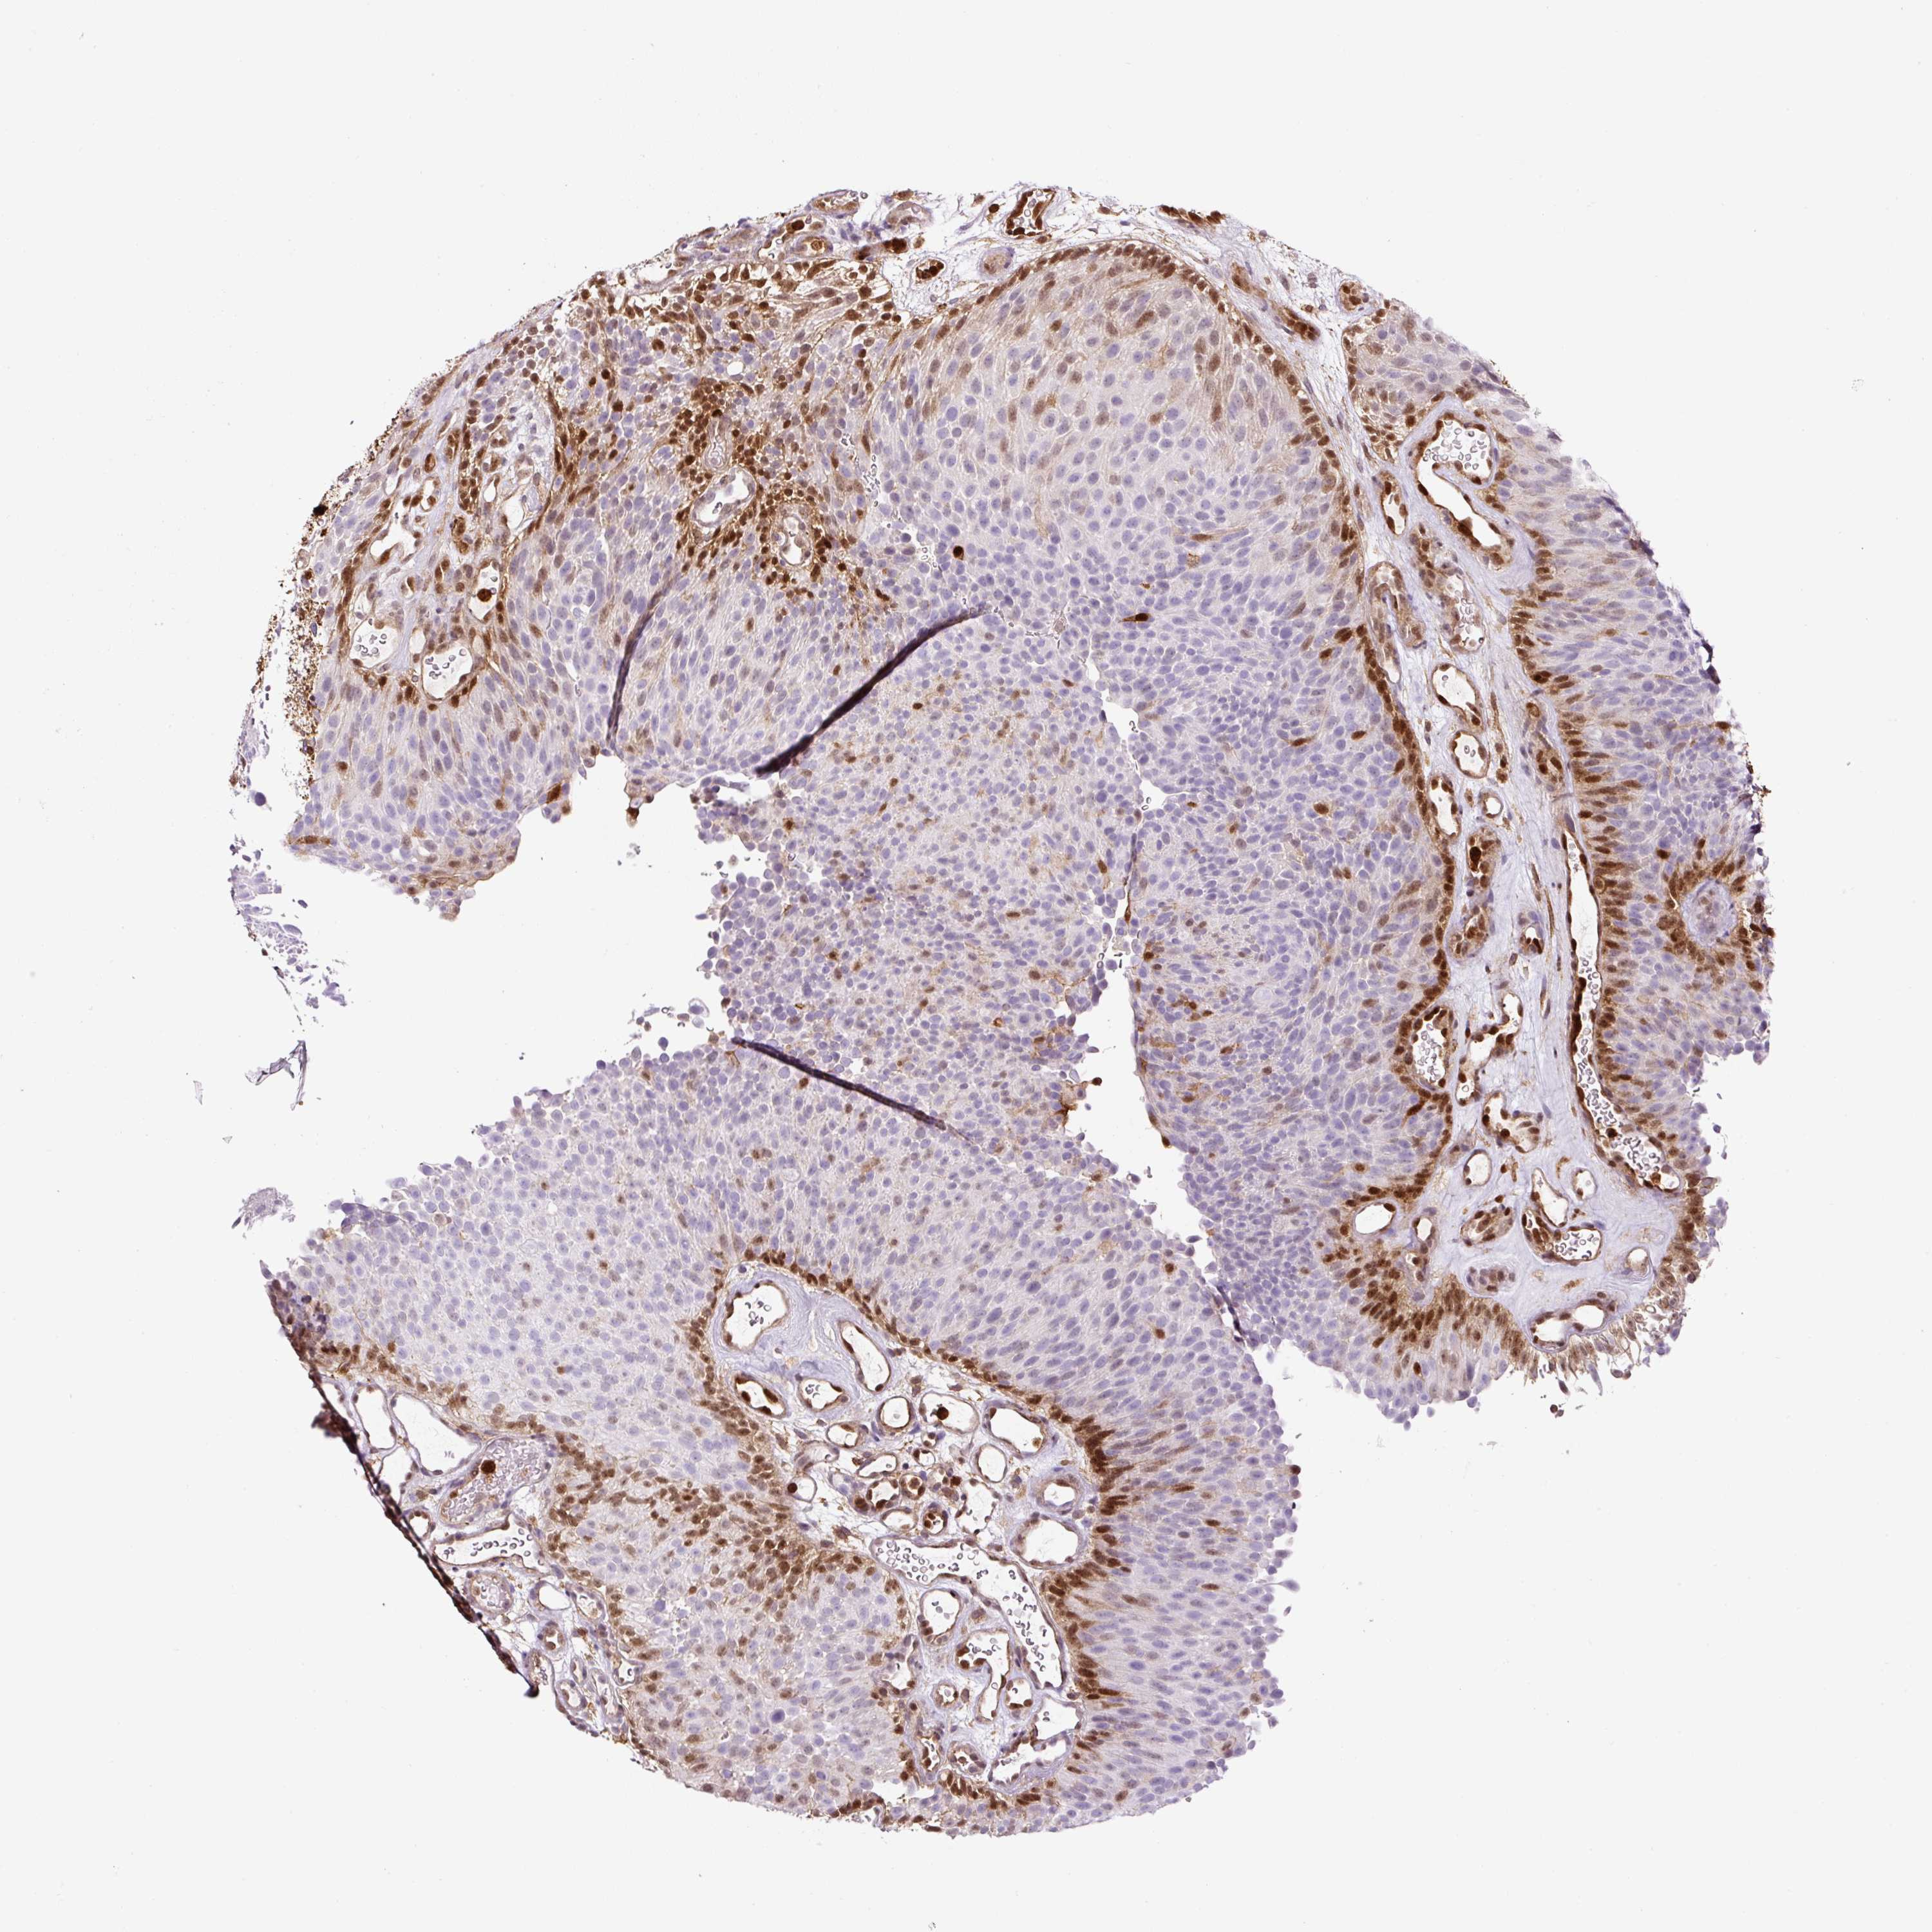

UROTHELIAL CANCER - Protein expressioni

A mouse-over function shows sample information and annotation data. Click on an image to view it in a full screen mode. Samples can be filtered based on level of antibody staining by selecting one or several of the following categories: high, medium, low and not detected. The assay and annotation is described here.

Note that samples used for immunohistochemistry by the Human Protein Atlas do not correspond to samples in the TCGA dataset.

Antibody stainingi

Antibody staining in the annotated cell types in the current human tissue is reported as not detected, low, medium, or high, based on conventional immunohistochemistry profiling in selected tissues. This score is based on the combination of the staining intensity and fraction of stained cells.

Each image is clickable and will lead to virtual microscopy that enables deeper exploration of all samples and also displays staining intensity scores, fraction scores and subcellular localization as well as patient and tissue information for each sample.

HPA011271

HPA011272

CAB013023

CAB035987

CAB058693

CAB080415

Staining

High

Medium

Low

Not detected

Intensity

Strong

Moderate

Weak

Negative

Quantity

>75%

75%-25%

<25%

None

Location

Nuclear

Cytoplasmic/membranous

Cytoplasmic/membranous,nuclear

Urothelial carcinoma, Low grade